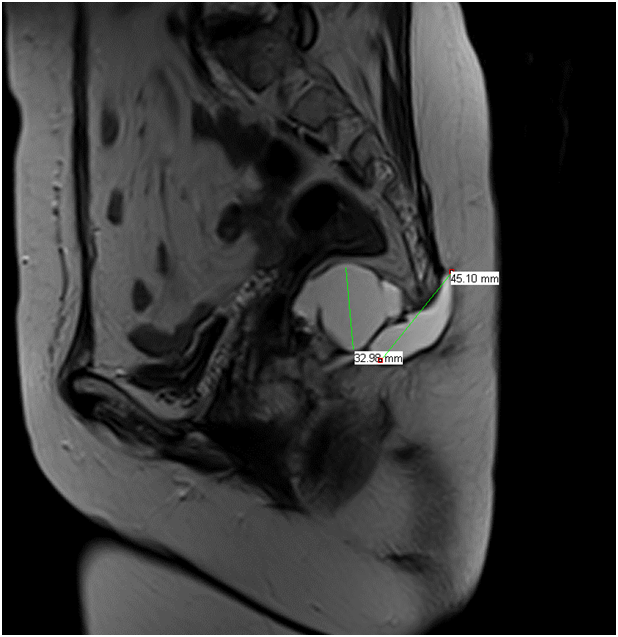

L’IRM de contrôle effectué le 13/5/2013, retrouvait un reste de la tumeur en retro ano rectale, ainsi qu’en rétro coccygien faisant respectivement 3,3cm et 4,5cm (fig3).

Figure3)IRM: Persistence tumorale en retro ano rectale ainsi qu'en rétro coccygien